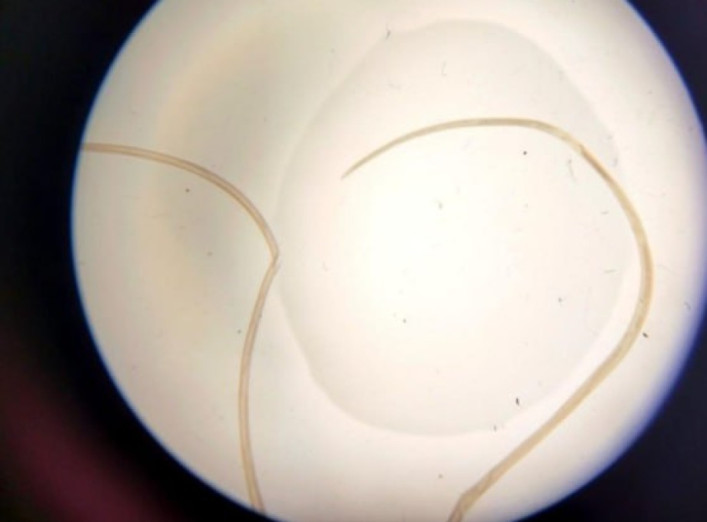

У Запоріжжі зафіксовано випадок дирофіляріозу — паразитарного захворювання, яке передається через укуси інфікованих комарів. У жінки личинка паразита потрапила під шкіру повіки. Про це повідомив Запорізький обласний центр контролю та

В місці укусу може виникнути інфікування ранки. Крім того, комахи можуть бути переносниками інфекційних хвороб: дирофіляріозу, малярії, туляримії, жовтої лихоманки, гарячки Денге, лейшманіозу тощо. -